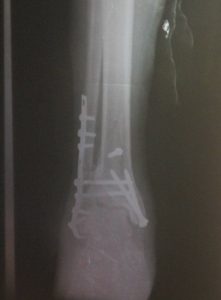

வீடுகளுக்கான அடிக்கல் நடுவதற்கு நாளையே – உடனடியான ஏற்பாடுகளை மேற்கொள்ளுமாறு பிரதேச செயலகத்தினர் அறிவுறுத்தியுள்ளனர். சத்தியகுமாரின் காணி சிறியது. தங்கியிருந்த தற்காலிகக் கொட்டிலை அகற்றினாலே வீடு அமைக்க முடியும். அதனையடுத்து இரவோடு இரவாக சத்தியகுமார் தற்காலிகக் கொட்டிலை அகற்றியுள்ளார்.எதிர்பாராத விதமாக கொட்டில் சரிந்து சத்தியகுமாரின் மேல் வீழ்ந்தது. அவர் படுகாயமடைந்த நிலையில் யாழ்ப்பாணம் போதனா மருத்துவமனையில் சேர்க்கப்பட்டார். அவருக்கு கால் முறிந்துள்ளது என்று மருத்துவர்கள் தெரிவித்துள்ளனர்.

அவருடைய காலில் தகடு வைக்கப்பட்டுள்ளது. ஆறு மாதங்கள் அவர் படுக்கையிலேயே இருக்க வேண்டும் என்றும் கூறியுள்ளனர்.வீடு அமைப்பதற்கு கடன் வாங்கி, கல் மற்றும் மண் போன்றவற்றை சத்தியகுமார் கொள்வனவு செய்துள்ளார். பிரதேச செயலகத்தால் நடத்தப்பட்ட கூட்டத்துக்குப் பின்னர் பிரதேச செயலகம் சத்தியகுமாருடனோ, அவரது மனைவியுடனோ தொடர்பு கொள்ளவில்லை.